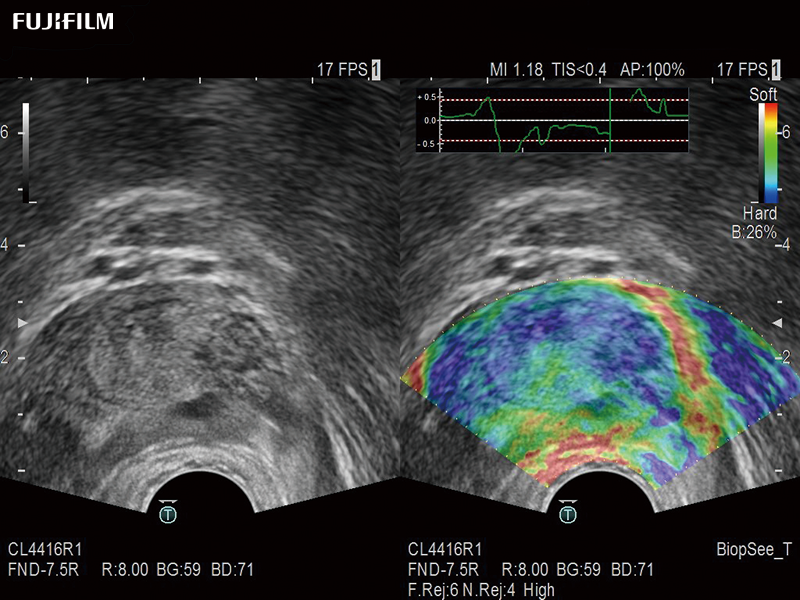

Bi-Plane transperineal biopsy transducer with simulataneous imaging and elastography capability.